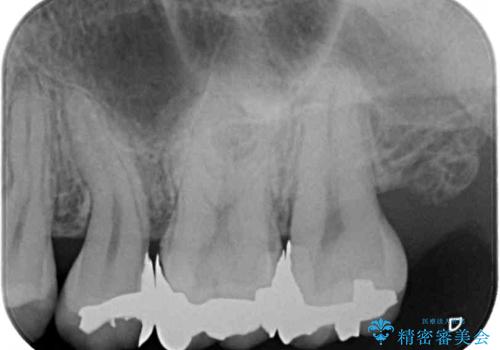

最近ものが挟まりやすくなったり、冷たいものがしみるようになったりといった症状があり、診査したところ、むし歯や歯質の欠損、不適修復物などが認められました。

精度の高いセラミックインレーによる修復治療を行うこととしました。

処置を行った歯以外にもむし歯と思われる歯が多数ありますが、費用のかかる治療であれば、優先順位をつけて、処置を急ぐ歯から処置を進めて行きました。